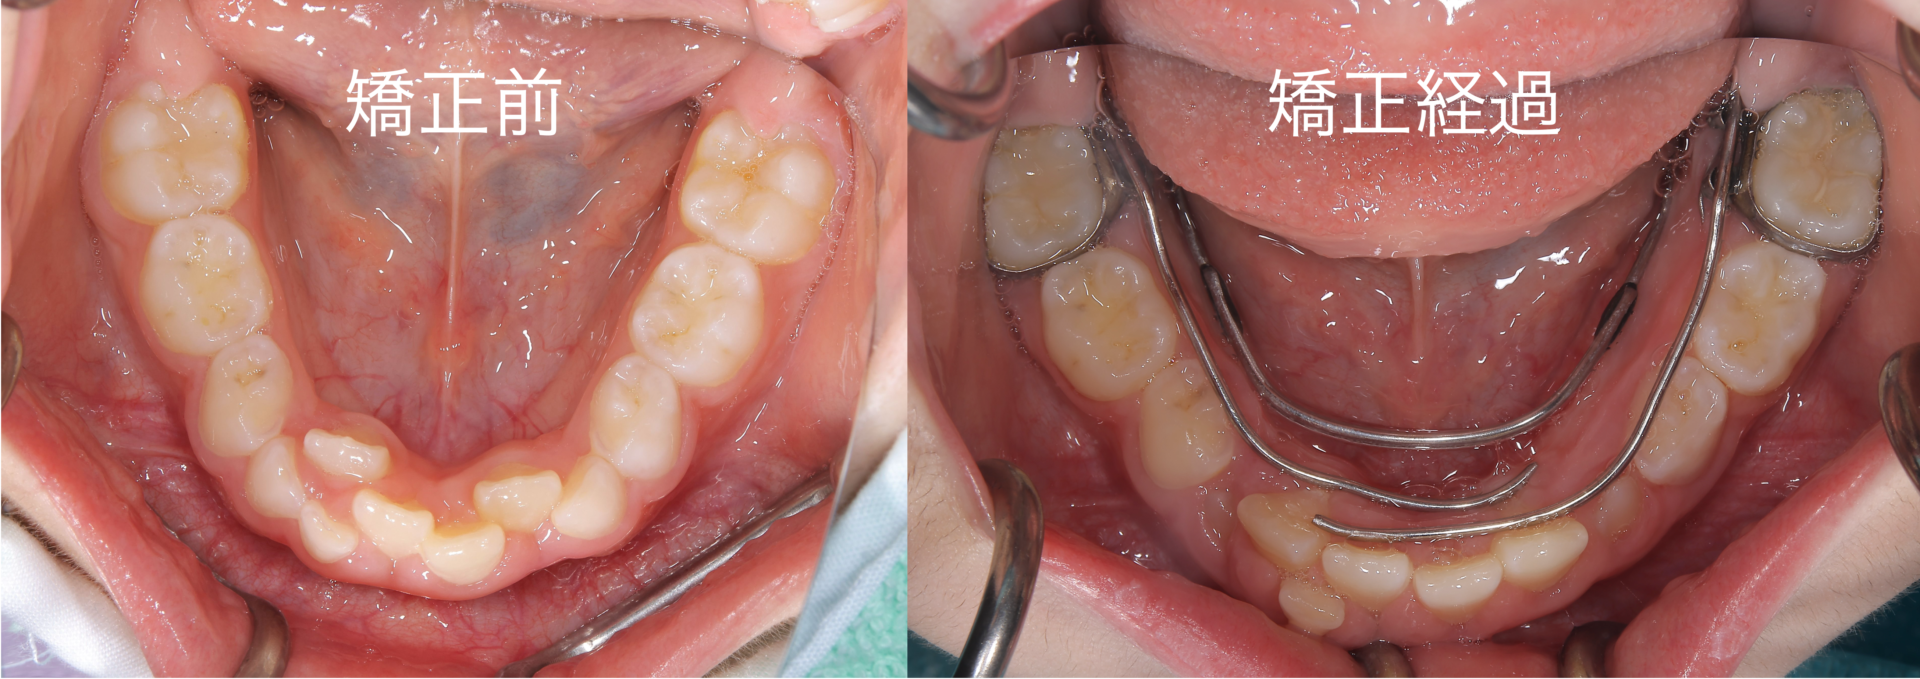

本日は、歯並びがガタついている8歳の患者様の治療経過を報告させていただきます 写真のように、特に下顎の前歯にガタつきが生じていましたこれから下顎の成長がありますが現状のガタつきは中程度以上と判断し、自然な成長では改善しない可能性が高いことを説明させていただいたところ、患者様は矯正治療(1期治療)を行い改善していかれることを希望されました 現状の評価と致しまし …